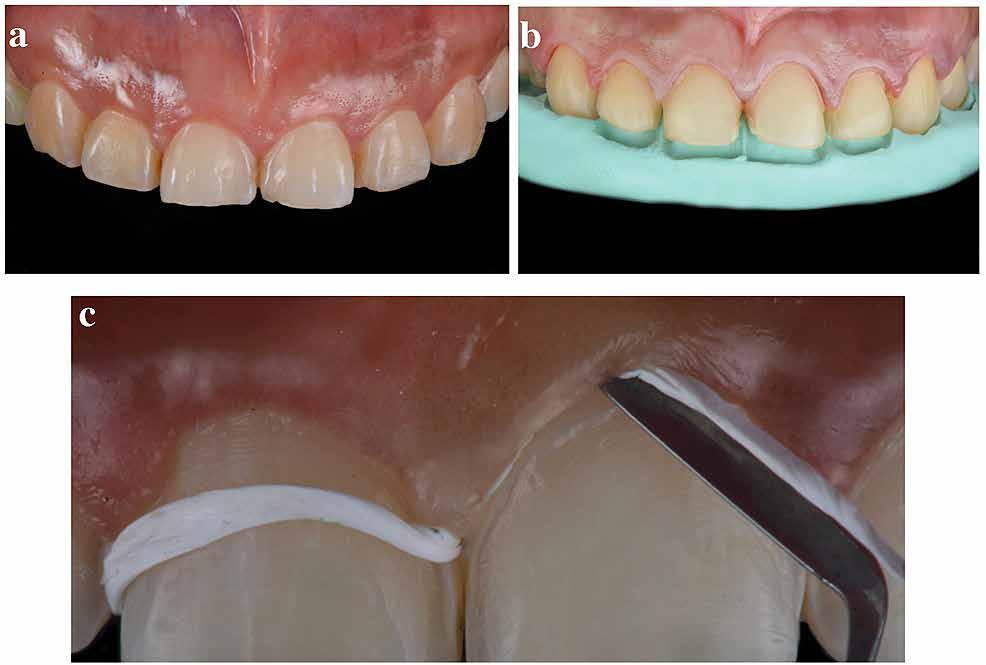

A front régióban alkalmazott minimál invazív multidiszciplináris megközelítés eredményeként jelentős mértékben tudtuk javítani a páciens esztétikai megjelenését. A beavatkozások során japán washi papír felhasználásával történő belső fogfehérítést, valamint háromdimenziós nyomtatással készült sebészeti sablon által vezetett ínyplasztikát végeztünk, majd az esztétikai zónában lévő fogakat – köztük egy elszíneződött nagymetsző fogat – ultravékony földpátkerámia héjakkal láttuk el.

A páciens elsősorban a mosolyának megjelenésén szeretett volna javítani. Egy előzetes állapotfelmérést követően az elszíneződött fog belső fehérítését, ínyplasztikát, valamint a felső front- és első kisőrlőfogak esztétikai célú helyreállítását javasoltuk. A belső fogfehérítés során nátrium-perborát és 30%-os hidrogén-peroxid keverékével átitatott washi papírt alkalmaztunk. Az anyag pulpakamrába történő helyezését követően az üreget üvegionomer cementtel zártuk. A fogfehérítés befejezését követően 3D nyomtatott sebészi sablont készítettünk, majd a felső front régióban megfigyelhető lágyrészek lefutását ezen sablon segítségével korrigáltuk. A sebészi beavatkozást követően 6 hónappal ultravékony földpátkerámia héjakat készítettünk.

A rendelésünkön jelentkező 40 éves nőbeteg a mosolyának esztétikai megjelenésén szeretett volna javítani (1. ábra)

A vizsgálat során a jobb felső első kisőrlőfog (1,4) és a bal felső első kisőrlőfog (2.4), valamint a köztük elhelyezkedő fogak kifejezett mértékű kopását észleltük (14-24). Ezen felül a felső metszőfogak (1.2–2.2) élei egyenetlen lefutással rendelkeztek, és a jobb felső nagymetszőfog (11) – amelyet korábban gyökérkezeltek és kompozit töméssel láttak el –jelentős színbeli eltérést mutatott. Az 1.4-es és 2.4-es fo-

A belső fogfehérítés utáni állapot.

gak között mért tasakmélység mértéke sehol sem haladta meg a 3 mm-t. A páciens számára belső fogfehérítést, ínyplasztikát és kerámia héjak készítését javasoltuk. A páciens a felajánlott kezelési tervet elfogadta. Első lépésként az 1.1es fog belső fogfehérítését terveztük, mivel a későbbiekben ezt a fogat is kerámia héjjal akartuk ellátni.

A korábban készített kompozit tömés eltávolítása (Round #2, Patterson Dental Co, 1031 Mendota Heights Road, Saint Paul, Minnesota, 55120, Egyesült Államok) kofferdám izolálásban történt (Nic Tone Dental Dam, MDC Dental, Guadalajara, Jalisco, Mexikó) (2. ábra). A tömés eltávolítása során a pulpa-szarvaknak megfelelő területet is feltártuk. Erre a fehérítés során elérhető legoptimálisabb végeredmény biztosítása érdekében volt szükség. A gyökértömés visszafúrását követően a gyökércsatornát lezáró guttaperchára (GP) egy vékony réteg (1 mm) üvegionomer cementet (GC Fuji IX GP, Tokió, Japán) helyeztünk annak érdekében, hogy a parodontális ligamentumok védelme a fehérítő anyag citotoxikus hatásaival szemben biztosított legyen. A cement kötése érdekében 8 percet vártunk, majd nátrium-perborát és 30%-os hidrogén-peroxid keverékét washi papírba (Washi Arts, Blaine, Washington, Egyesült Államok) csomagoltuk, és azt az üregbe helyeztük (3. és 4. ábrák) Végezetül a zománcszéleket foszforsavval kondicionáltuk, és az üreget üvegionomer cement segítségével lezártuk. A pácienst két héttel később hívtuk vissza kontrollra és a fehérítő anyag kicserélésére. Ezt a lépést 2 hét múlva megismételtük. Ebben az időpontban a fog színbeli eltérése már nem volt észlelhető. A kérdéses fog színe jelentősen kedvezőbbé vált. Az üreg végleges lezárása során szendvics technikát alkalmaztunk. A tömés elkészítéséhez hagyományos üvegionomer cementet (GC Fuji IX GP) és folyékony kompozitot (G-ænial Universal Flow, GC) használtunk. Az üvegionomer cement kötését követően a cementet 1 mm mélységig visszafúrtuk, majd foszforsavas kondicionálást követően ezt a sekély üreget univerzális bonddal fedtük, és

3. ábra: A fehérítő anyagok összekeverése és washi papírba történő csomagolása. (A): Az anyagok összekeverése. (B): A keverék washi papírra történő helyezése. (C): A keverék washi papírba történő becsomagolása. (D): Ideiglenes zárás.

5. ábra: A 3D nyomtatással készült sebészi sablon ínyplasztika során való alkalamzása. (A): A sablon digitális tervezése. (B): Az elkészült sablon helyére illesztése. (C): Az ínyplasztika sablon segítségével történő kivitelezése. (D): A műtét utáni állapot.

a polimerizálást követően folyékony kompozittal töltöttük fel. A páciens elégedett volt az eddig elért eredményekkel, és beleegyezett abba, hogy folytassuk a kezelést, amelynek következő lépése az ínyplasztika volt.

Mivel a rendelkezésünkre álló feszes íny szélessége lehetővé tette, ezért koronahosszabbítás helyett ínyplasztika végzése mellett döntöttünk. Először diagnosztikus gipszmintákat készítettünk, majd felviaszolás, azaz a wax-up (Wax GEO Classic, Renfert, Hilzingen, Németország) segítségével meg-

Az ultravékony héjpreparálás menete. (A): Az előkészítés mélységének ellenőrzése átlátszó redukcióssablon segítségével. (B): Az eltávolított anyag vastagságának ellenőrzése gyúrható szilikonból készült sablon segítségével. (C): Az okkluzális irányú redukció szilikonsablonnal történő ellenőrzése.

terveztük a páciens igényeinek megfelelő harmonikus mosoly biztosításához szükséges fogformákat és az ínylefutást. A diagnosztikus wax-up szkennelését (D2000, 3Shape A/S, Koppenhága, Dánia) követően digitálisan megterveztük a sebészi sablont, és azt 3D nyomtató segítségével (Form 3, FormLabs) rezinből (Dental LT Clear Resin V2, Form 2, FormLabs, Somerville, Massachusetts, Egyesült Államok) elkészítettük (4. ábra). A sebészi sablon fogakra történő helyezését követően egyértelműen látszott, mely vonalban kell az

7. ábra. A héjak vastagságának ellenőrzése és a felületek előkészítése. (A): A héjak vastagságának ellenőrzése. (B): A mérés eredményének ellenőrzése: 0,5 mm-nél vékonyabb. (C): Hidrofolysavval történő kondicionálás. (D): A primer applikálása.

ínyplasztikát vezetnünk. Az ínyplasztikához elektrokautert (Sensimatic 700SE Electrosurge, Parkell Inc, Edgewood, New York, Egyesült Államok) használtunk (5. ábra). A papillák védelme érdekében az interproximális területnek megfelelően elektrokauter helyett parodontális kést (KB5/6 Buck Periodontal Knife, Hu-Friedy, Chicago, Illinois, Egyesült Államok) alkalmaztunk az interdentálisan elhelyezkedő ínyrészek újrakontúrálására.

Ezt követően 6 hónapot vártunk a parodontális szövetek gyógyulásának érdekében. Ekkor a mock-up-ot felhelyeztük a páciens fogaira. Mivel a páciens elégedett volt a bemutatott látvánnyal, ezért a kezelés következő fázisának megkezdése mellett döntöttünk. A preparálás előtt a fogak felszínén mélységjelölő barázdákat alakítottunk ki (LVS1 FG Medium Depth Cutting Diamond 834.31.021, Brasseler Dental, One Brasseler Boulevard Savannah, Georgia 31419, Egyesült Államok). A megfelelő anyagvastagság biztosításához ezen felül egy 0,5 mm vastagságú átlátszó redukciós sablont (Keystone Industries, 480 South Democrat Road, Gibbstown, New Jersey, Egyesült Államok) is készítettünk. A sablont egy vákuumkészülék (Pro-Vac Machine 110V, Keystone Industries) segítségével hoztuk létre. A protetikai fázis során a frontfogak és az első kisőrlőfogak kerámia héjakkal történő ellátását terveztük. A preparálás mélységét a sablon felhelyezését követően, a sablonon lévő perforációk segítségével tudtuk ellenőrizni. A nyílásokba parodontális szondát vezettünk, hogy meghatározzuk a redukció mértékét (6. ábra). A preparálás megfelelőségét ezen felül egy gyúrható szilikonból készült sablonnal is ellenőriztük. Ebben az esetben is parodontális szondát használtunk a mélység ellenőrzése céljából (6. ábra). A csonkelőkészítés utolsó lépéseként a lecsiszolt fogfelszíneket polírkorongok segítségével (OptiDisc, Kerr, Orange, Kalifornia, Egyesült Államok) simára políroztuk. A lenyomatvétel során duplafonalas lenyomatvételi technikát alkalmaztunk. Az ínybarázdákba először #00-

8. ábra. Az ultravékony héjak adhezív módszerekkel történő ragasztása. (A): Az elkészült héjak. (B): A fogfelszínek kofferdám izolálásban történő foszforsavas kondicionálása. (C): Az adhezív felvitele. (D): A héjak fényre kötő rezin alapú ragasztócementtel történő ragasztása.

ás, majd #0-ás retrakciós fonalakat (Ultrapak, Ultradent Products Inc, South Jordan, Utah, Egyesült Államok) helyeztünk. A végső precíziós lenyomatot polivinil-sziloxán lenyomatanyaggal (Virtual 380, Ivoclar Vivadent AG, Schaan, Liechtenstein) vettük. A fogtechnikai fázisban ultravékony (0,5 mm-nél vékonyabb) földpátkerámia héjak elkészítését kértük (Super Porcelain Ex-3, Kuraray Noritake Dental, Tokió, Japán), (7. ábra). A kerámia héjak készre vitelét követően a próba során a héjakat a helyükre illesztettük a széli zárást, az így kialakított fogformák ellenőrzése céljából. A páciens elégedett volt az így kapott látvánnyal. A végleges ragasztás kofferdám izolálásban történt. A preparált fogak felületét először 37%-os foszforsavval (Total Etch, Ivoclar Vivadent) 15 másodpercen keresztül kondicionáltuk, majd vízzel leöblítettük (8. ábra). A kondicionált zománcfelszíneket Adhese Universal (Ivoclar Vivadent) adhezívvel kezeltük. A kerámiahéjak homorú felszíneit 5%-os folysavval (IPS Ceramic Etching Gel, Ivoclar Vivadent) 20 másodpercen át kondicionáltuk, majd a felszíneket Monobond Plus primerrel (Ivoclar Vivadent) vontuk be (7. és 8. ábrák). A héjakat fényre kötő rezinalapú ragasztócement (Variolink Esthetic LC, Ivoclar Vivadent) applikálását követően a helyükre illesztettük. A kifolyó cementfelesleg eltávolítását követően minden felszínt (labiális, palatinális, meziális és distális) LED-es polimerizációs lámpával (VALO Cordless, Ultradent) 40 másodpercen keresztül megvilágítottuk.

A páciens elégedett volt a végleges restaurátumok színével, formájával és méretével. A kezelés végeredménye kielégítette az esztétikai elvárásait (9. ábra). A frissen átadott restaurátumok épségének megőrzése érdekében a páciens számára éjszakai fogvédősínt készítettünk. A páciensünk a négyéves kontrollvizsgálat során is nagyon elégedett volt a kezelés eredményével. A korábban meglévő fekete háromszögek eltűnésének különösképpen örült (9. és 10. ábrák)

9. ábra. A beavatkozás után, valamint a 4 évvel később látható állapot. (A): Egy héttel a ragasztás után készült felvétel. (B): A négyéves kontroll alkalmával készült felvétel.